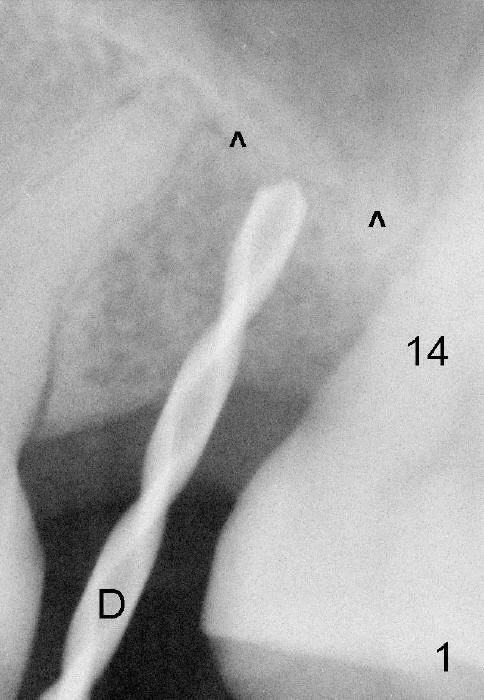

Exam immediately prior to surgery shows that the edentulous ridge is wide buccolingually. The mesiodistal space is less than 6 mm. It appears that a 4 mm implant is appropriate. Two piece implant is chosen over a one-piece one, because of large surface area of the former. After local anesthesia, a 3.5 mm tissue punch is used for access to the bone. A 1.5 mm pilot drill initiates osteotomy 8 mm in length (Fig.1 D). The drill is more or less in the middle of the edentulous space and 1 mm coronal to the sinus floor (^). Then a 2 mm pilot drill, 2.5 mm and 3 mm reamers are used to enlarge osteotomy (8 mm deep). Mixture of autogenous bone and Osteogen and 2.5 mm Bicon osteotome are used for sinus lift. The osteotome does not reach the intended depth of 10 mm. The osteotomy is extended with the 2 mm drill and 2.5 mm reamer (Fig.2 R) to barely perforate the sinus floor. When a 4x11 mm implant is being placed, it tends to deviate distally. The implant is backed up twice: initially it appears to lean mesially, but as it is seated deeper, it is deviated distally again (Fig.3). An immediate provisional has to be fabricated to prevent the space from further narrowing. A 3.5x3 mm abutment is placed. The mesial surface of the tooth #14 (Fig.4 black area) is trimmed for restoration. Why is the implant deviated? How to fix it?